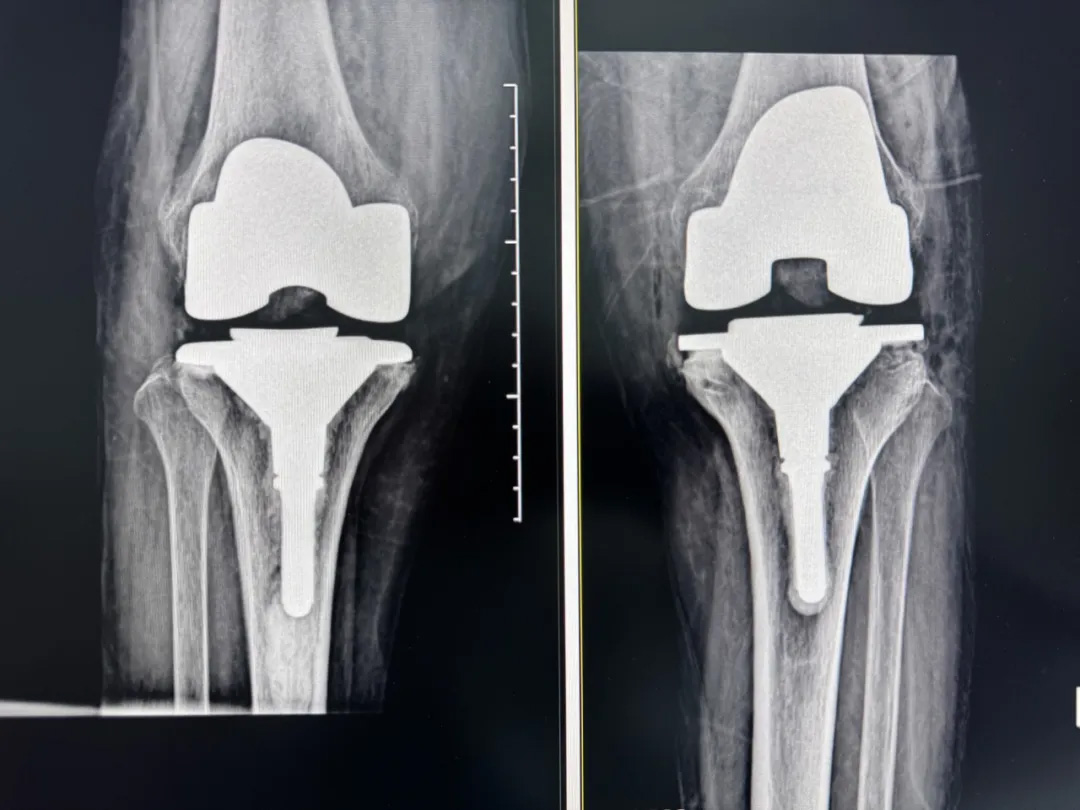

術(shù)前:AI通過CT掃描生成毫米級(jí)膝關(guān)節(jié)三維模型,為假體安裝設(shè)計(jì)出誤差小于1毫米的精準(zhǔn)方案 術(shù)中:智能導(dǎo)航系統(tǒng)如同"透視眼",引導(dǎo)醫(yī)生避開密集的神經(jīng)血管網(wǎng),截骨更精準(zhǔn),出血僅100ml 術(shù)后:當(dāng)天鄭阿婆即開始抬腿的康復(fù)訓(xùn)練,24小時(shí)內(nèi)扶助行器下地行走,三天后已能在病房走廊獨(dú)立行走,完成洗漱用餐 兩周后健步出院時(shí),女兒含淚感慨“之前擔(dān)心她年紀(jì)大扛不住手術(shù),沒想到恢復(fù)這么快!現(xiàn)在每天散步比我還精神。知道技術(shù)這么先進(jìn),真該早點(diǎn)來!”

"這就像給傳統(tǒng)手術(shù)裝上了自動(dòng)駕駛系統(tǒng)。"主刀醫(yī)生羅軍副院長(zhǎng)用生動(dòng)比喻解析技術(shù)突破。AI不僅實(shí)現(xiàn)假體“量身定制”,使用壽命可達(dá)20年以上,更通過三維路徑規(guī)劃將康復(fù)周期壓縮,實(shí)現(xiàn)術(shù)后24小時(shí)下地,2周回歸正常生活。同時(shí),AI會(huì)避開重要組織,具有出血少、感染風(fēng)險(xiǎn)低的特點(diǎn)。專家特別提醒,當(dāng)出現(xiàn)夜間持續(xù)性關(guān)節(jié)疼痛、步行能力低于10分鐘或關(guān)節(jié)畸形時(shí),應(yīng)及時(shí)就醫(yī)評(píng)估,"別等到關(guān)節(jié)'報(bào)廢'才手術(shù)"。